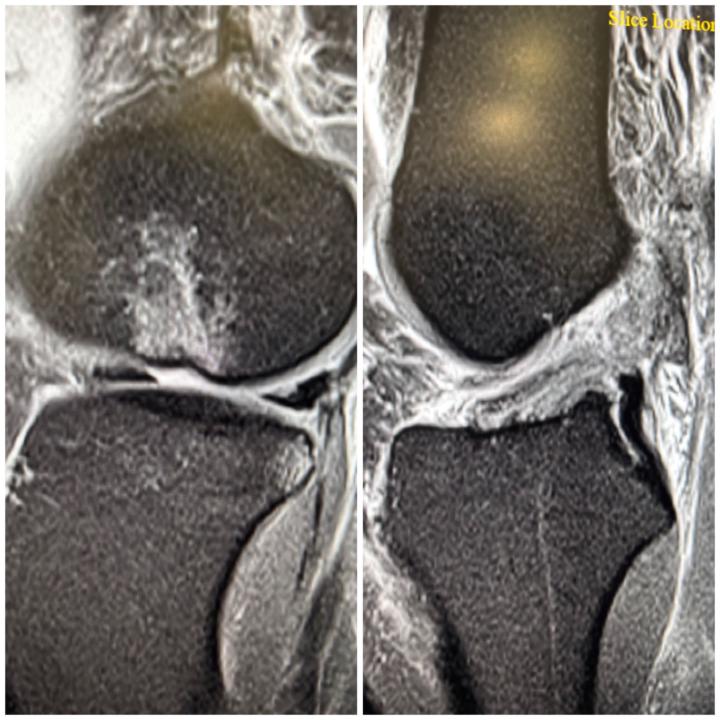

Trochlear dysplasia with MPFL tear

✅✅"Case Spotlight: Trochlear Dysplasia with Patellar Dislocation and MPFL Tear on MRI As a radiologist, I'd like to share a complex case involving trochlear dysplasia, patellar dislocation, and a tear of the medial patellofemoral ligament (MPFL). Clinical Presentation:🌟 - Recurrent patellar dislocations - Knee pain and instability MRI Findings:✅ - Trochlear dysplasia with a shallow femoral trochlea - Patellar dislocation with lateral patellar tilt - Complete tear of the MPFL - Associated bone marrow edema and soft tissue injuries Trochlear dysplasia is a critical factor in patellar instability, and MPFL tears are a common consequence of patellar dislocation. Key takeaways:⚜️⚜️ - MRI is essential for diagnosing trochlear dysplasia and MPFL tears - Accurate diagnosis guides surgical planning and reconstruction - MPFL reconstruction is often necessary to restore patellar stability✅